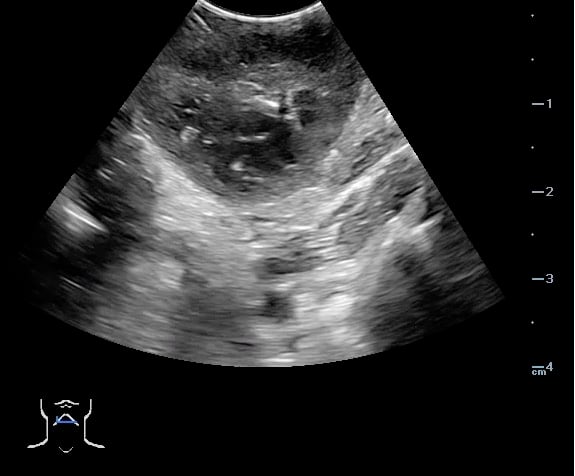

Peritonsillar abscess (PTA)33,34

- Significance of pathology:

- Complications of a PTA may include development of a parapharyngeal abscess, mediastinitis, airway obstruction, and other life-threatening pathology.

- Incidence of pathology:

- 37 per 100,000 PTA33,34

- Peritonsillar abscess is visualized as a hypoechoic or complex cystic structure